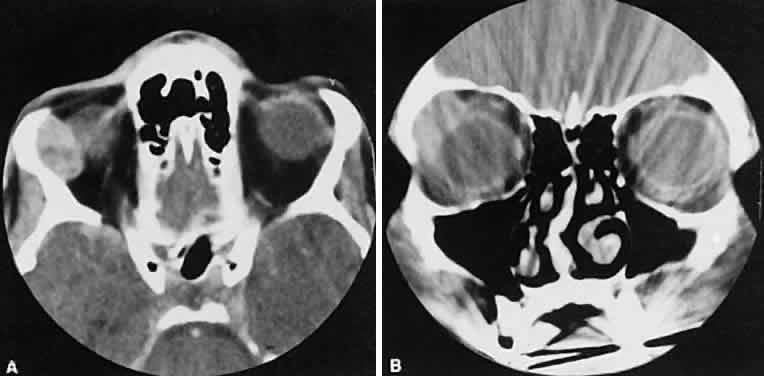

Both cavernous hemangiomas (Fig. 14) and hemangiopericytomas typically are seen in adults. Their radiographic appearance is similar and shows a well-demarcated, contrast-enhancing mass, although more intense enhancement may be seen with the hemangiopericytoma. The differential diagnosis of a well-demarcated, contrast-enhancing lesion is listed in Table 3.

Fig. 14. Axial (A) and coronal (B) views of a cavernous hemangioma depicted as a hyperdense-enhancing, well-circumscribed mass.

Fig. 16. Benign mixed tumor of the lacrimal gland. Axial (A) and coronal (B) views show a well-demarcated hyperdense mass that expands the fossa of the lacrimal gland by pressure effects rather than erosion. Suggestion of mixed density is apparent on the axial view, and globe displacement is evident on the coronal view.

Lymphomatous involvement of the lacrimal gland resembles inflammatory dacryoadenitis radiographically. The enlarged lacrimal gland conforms to the shape of the globe, and the adjacent bone is normal (Fig. 18). We are aware of three high-grade lymphomas that affected the orbit and lacrimal gland and indented the globe, but this is distinctly unusual. Non-Hodgkin's B-cell lymphomas represent the most common type of lymphoma to affect the orbit. Literally any structure in the orbit can be subject to lymphomatous involvement; therefore, a lymphoma should be suspected in the presence of any amorphous isointense infiltrative process.

Fig. 18. Axial (A) and coronal (B) views of lacrimal gland lymphoma. There is homogenous enhancement of the enlarged lacrimal gland. Compared with Fig. 6, there is no difference.